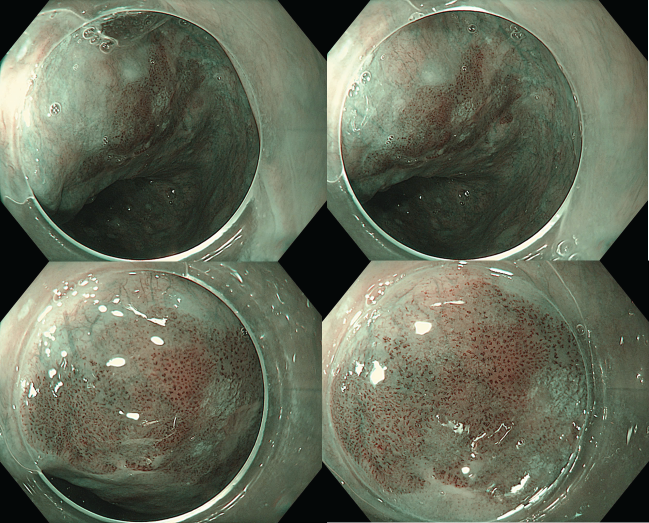

Quan sát với NBI, tổn thương hiện rõ màu nâu đậm hơn so với niêm mạc xung quanh, có dấu hiệu của “vùng màu nâu” brownish color (BC+). Ranh giới tổn thương được xác định rõ ràng. Cấu trúc vi mạch theo phân loại JES cho thấy type B1 – đặc trưng bởi các mạch máu dạng vòng nhỏ (loop-like), xuất hiện như các chấm, gợi ý tổn thương nông T1a-EP/LPM.